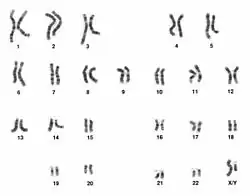

PUBS is not a diagnostic test that is indicated in every pregnancy. It is, however, suggested in pregnancy cases in which the blood gas levels and pH would aid in diagnosis of a condition, such as anemia, or delivery plan, if termination of the pregnancy is being considered or special plans must be made. Umbilical cord blood gas analysis may assist with clinical management and excludes the diagnosis of birth asphyxia in approximately 80% of depressed newborns at term.[27] Severe fetal growth issues in conjunction with low oxygen in the fetus’ blood and high levels in the mother’s blood also indicate the use of PUBS.[28] With more detailed observations and information on fetal tissue perfusion and metabolism, better predictions on development can be made. For pregnancies in which genetic abnormalities may be present, PUBS can be used to construct a karyotype, usually within 48 hours, and detect irregular chromosomal patterns.[2] Karyotypes are able to confirm or detect monosomies, trisomies, or missing portions of chromosomes to give a detailed picture of the severity of the genetic defect as well as predicting developmental future. PUBS is also indicated in the cases of twins with accumulation of amniotic fluid and substantially different growth rates (at least 10%), if the fetus is expected to be breaking down red blood cells improperly, and in the alleviation of hydrops fetalis, a build-up of fluid in at least 2 parts of the fetus.[28] Suspicion of fetal infections, such as rubella and toxoplasmosis, as well as the need to supply medicine or blood transfusions to the fetus are indications for the use of PUBS.[2]